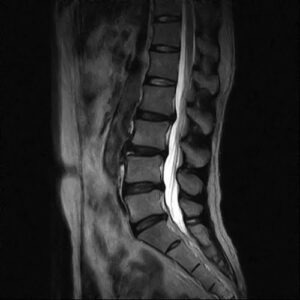

ヘルニアの画像診断

腰椎椎間板ヘルニアは下記の画像の矢印部分のような軟骨の飛び出しが見られます。